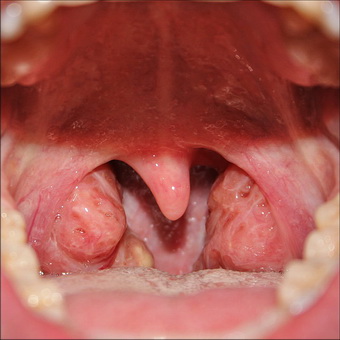

Гипертрофия небных миндалин, фото которой можно увидеть ниже, является своеобразной адаптацией организма:

Принято различать три степени гипертрофии небных миндалин в зависимости от того насколько развит процесс и увеличены гланды. Определить размер и степень их гипертрофии может только ЛОР-врач при осмотре горла. Степень развития заболевания зависит от величины гланд, а точнее от того насколько много осталось свободного пространства между краем передней нёбной дужки и средней линией глотки.

Гипертрофия небных миндалин 1 степени диагностируется в том случае, когда занята 1/3 часть пространства. Такие изменения чаще всего обнаруживаются случайно, так как они пока еще не вызывают никаких дискомфортных ощущений у ребенка.

Когда имеет место гипертрофия небных миндалин 2 степени, воспаленные органы занимают уже 2/3 всего пространства и вызывают первые признаки болезни (изменение голоса, трудности с дыханием).

При гипертрофии небных миндалин 3 степени воспаленные органы занимают практически все пространство и даже могут соприкасаться друг с другом.